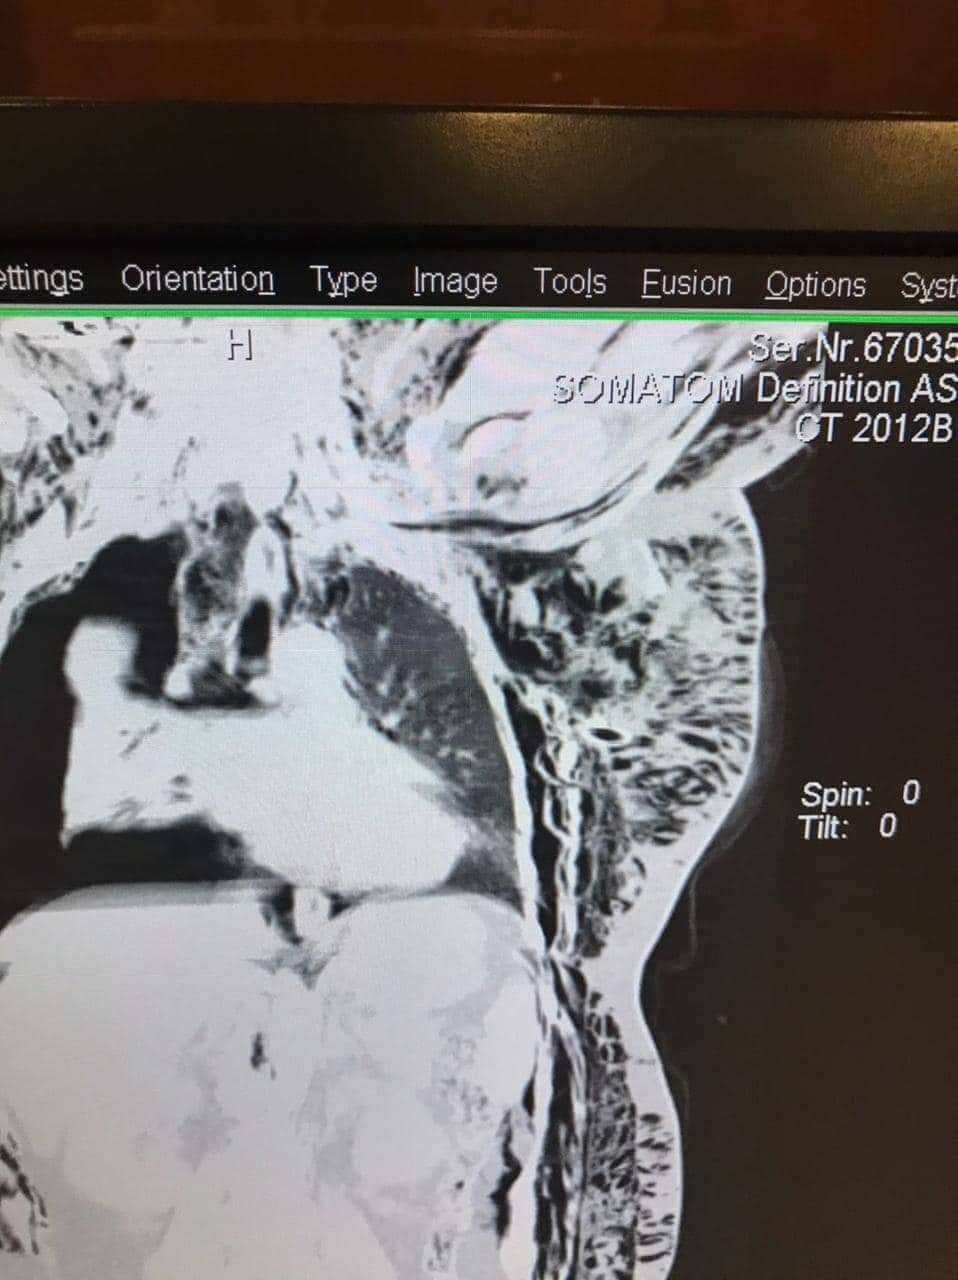

بالصور.. فريق جراحي بمدينة الصدر الطبية ينقذ حياة شابة بعد انفصال إحدى رئتيها من القصبة الهوائية

نجح فريق جراحي في مدينة الصدر الطبية التابعة لدائرة صحة النجف الاشرف، اليوم الخميس، بإنقاذ حياة شابة تعرضت لحادث سير أدى إلى تهشم عدد من أضلاعها وانفصال الرئة اليمنى تماما من القصبة الهوائية.

وبين رئيس الفريق الجراحي الدكتور منتظر الحكيم اختصاص جراحة القلب والصدر والأوعية الدموية في تصريح تابعته “النعيم نيوز”. أن “الفريق الجراحي نجح بإجراء عملية طارئة وفوق الكبرى لإعادة الرئة الى الجهاز التنفسي واستعادة تنفسها الطبيعي الذي عاد وبالعلامة الكاملة (100%)”.